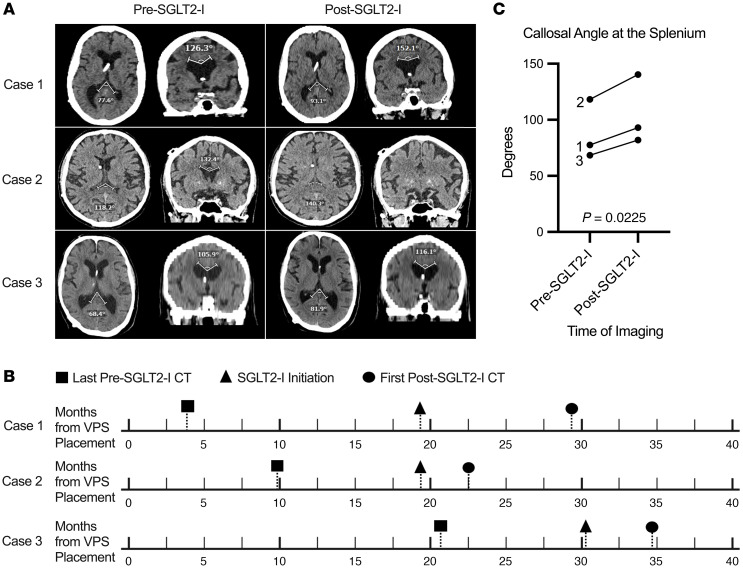

Impact of SGLT2 inhibitors on cerebrospinal fluid dynamics and implications for hydrocephalus management.

SGLT2抑制剂对脑脊液动力学的影响及其对脑积水治疗的影响